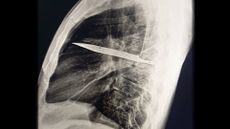

Diagnostic dilemma: A fish bone wandered through a man's abdomen and stabbed his liver

By Mindy Weisberger published

A man went to the hospital several times with gut pain and a fever — and it turned out that his relatively common symptoms had an unusual cause.